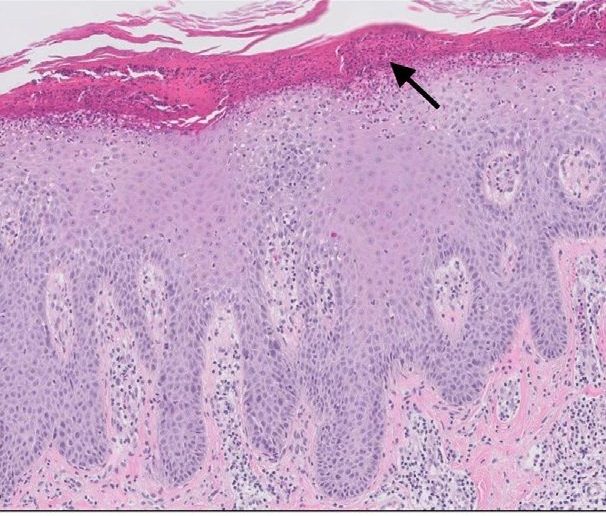

Histological Characteristics

Acanthosis

Parakeratosis with neutrophil aggregation

Alternating hypogranulosis and hypergranulosis

Absence of granular lesions

Dilated and tortuous capillaries in the dermis